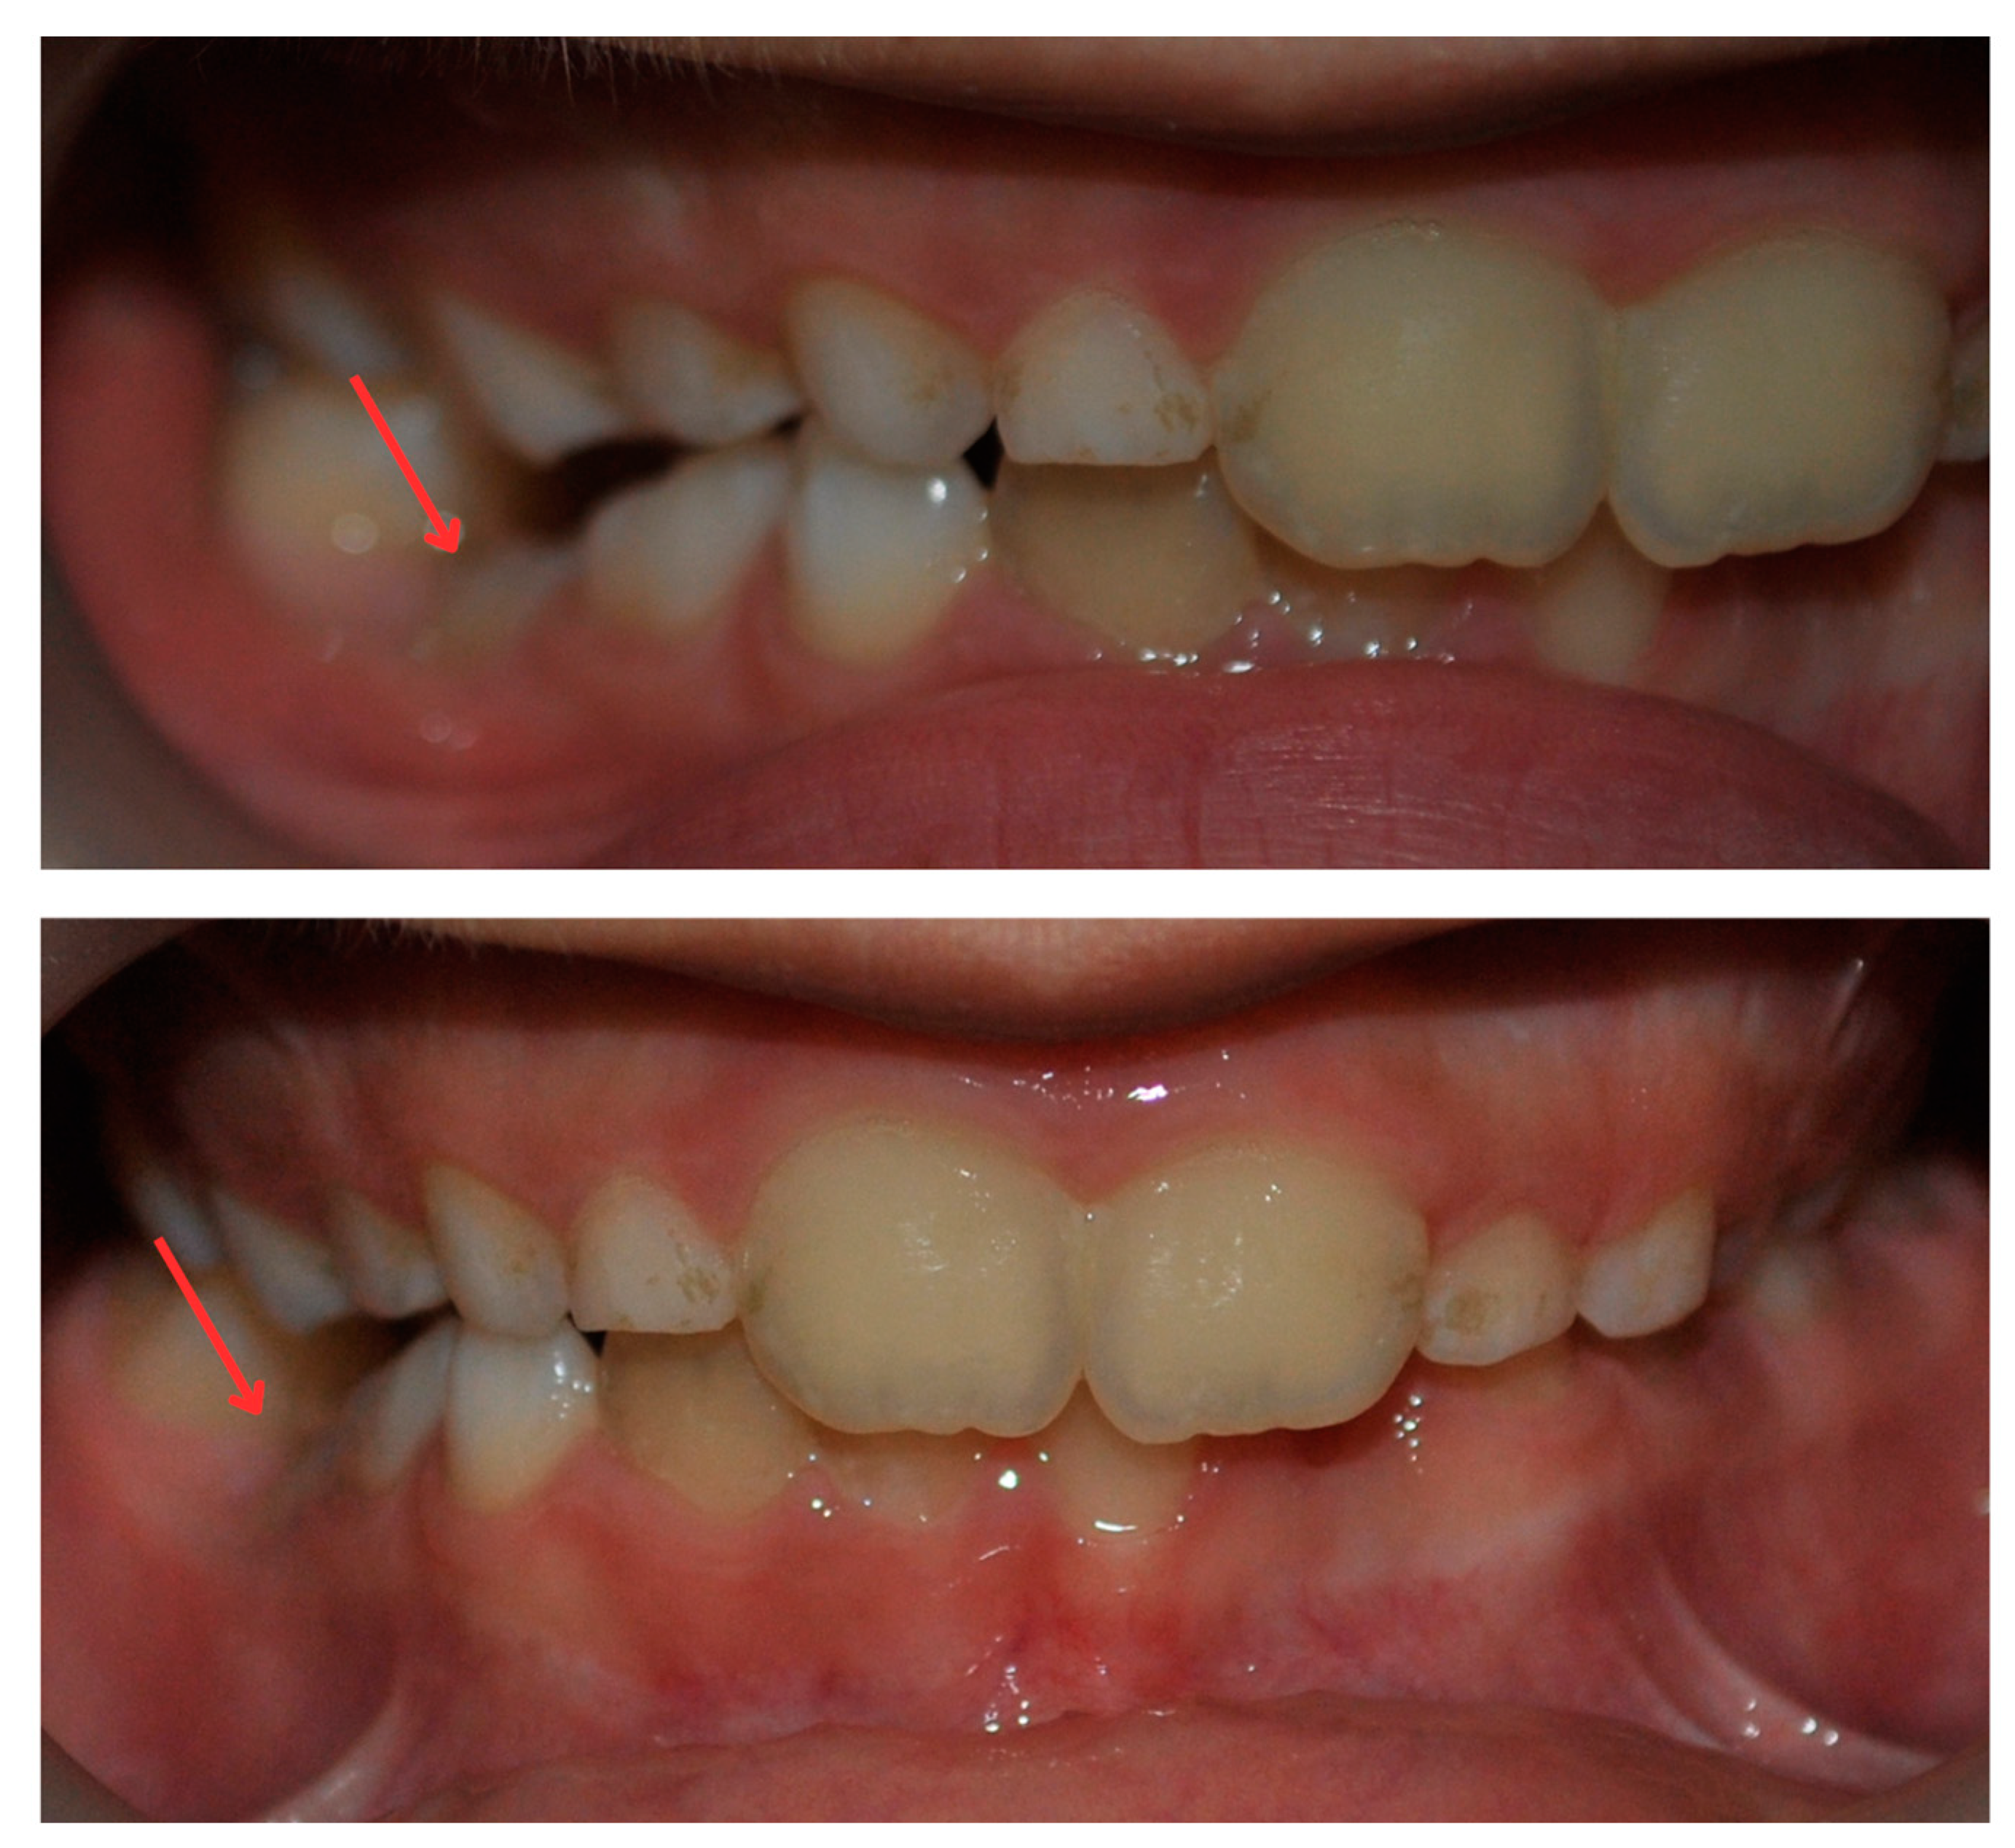

2. Case Report

2.1. Examination, Diagnostics, and Initial Therapeutic Management